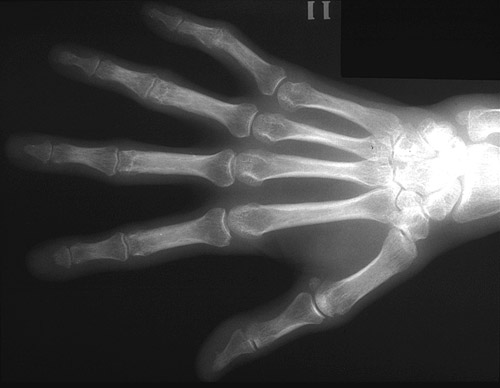

| Most cases of Turner syndrome (monosomy X, with a 45, X karyotype) result in fetal loss. However, a handful of persons (probably with some degree of mosaicism) may live to adulthood. One of the features is a short fourth and/or fifth metacarpal bone. |